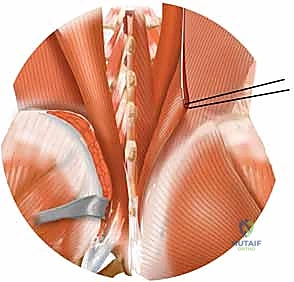

2. الفتح الجراحي والوصول الآمن (Surgical Exposure)

تحت التخدير العام، يتم إجراء شق جراحي دقيق. هنا تتجلى خبرة الدكتور هطيف في تجنب الأوعية الدموية الكبيرة والأعصاب الحساسة المحيطة بالحوض. يتم فصل العضلات بلطف للوصول إلى العظام المكسورة.

كلمة "الرد" تعني إعادة العظام المكسورة أو المفاصل المخلوعة إلى موضعها التشريحي الأصلي (Anatomical Alignment). باستخدام أدوات جراحية متخصصة وملاقط عظمية، يقوم الدكتور هطيف بإعادة تجميع قطع العظام المتناثرة وكأنها "أحجية معقدة"، مع التأكد من تحرير أي أعصاب مضغوطة باستخدام تقنيات الجراحة الميكروسكوبية إذا لزم الأمر.